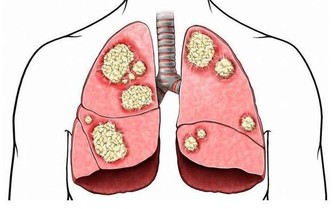

中老年人(45歲以上),由於身體機能的下降和免疫能力逐漸降低,成為我國發病率最高的人群。同樣,也是患癌風險最高的人群。而我國,發病率和死亡率最高的癌症,當屬肺癌!所以,提防肺癌的發生是當務之急!有這「五個信號」的人們,要及時到醫院做檢查,以免耽誤治療!

1、長期咳嗽、痰中帶血

腫瘤生長於管徑較大、對外來刺激落敏感的段以上支氣管黏膜時,可產生類似異物樣刺激引起的咳嗽,典型的表現為陣發性刺激性乾咳,一般止咳藥常不易控製。由於腫瘤組織血供豐富,質地脆,劇咳時血管破裂而致出血。肺癌咳血的特徵為間斷性或持續性、反覆少量的痰中帶血絲,或少量咯血,偶因較大血管破裂導致難以控製的大咯血。

2、低熱

肺癌所致的發熱原因有兩種,一為炎性發熱,癌腫瘤生長時,常先阻塞段或支氣管開口,引起相應的肺葉或肺段阻塞性肺炎或不張而出現發熱,但多在38℃左右,很少超過39℃。

二為癌性發熱,多由腫瘤壞死組織被機體吸收所致。

3、胸痛

常表現為胸部不規則的隱痛或鈍痛。大多數情況下,周圍型肺癌侵犯壁層胸膜或胸壁,可引起尖銳而斷續的胸膜性疼痛,若繼續發展,則演變為恆定的鑽痛。

持續尖銳劇烈、不易為藥物所控製的胸痛,則常提示已有廣泛的胸膜或胸壁侵犯。肩部或胸背部持續性疼痛提示肺葉內側近縱隔部位有腫瘤外侵可能。

4、胸悶、氣短

引起呼吸困難的原因主要包括:

①肺癌晚期,縱隔淋巴結廣泛轉移,壓迫氣管

②大量胸腔積液時壓迫肺組織也可出現胸悶、氣急、呼吸困難,但抽液後癥狀可緩解。

③瀰漫性細支氣管肺泡癌和支氣管播散性腺癌,使呼吸面積減少,氣體彌散功能障礙,導致嚴重的通氣/血流比值失調,引起呼吸困難逐漸加重,常伴有發紺。

5、消瘦

肺癌晚期由於感染、疼痛所致食慾減退,腫瘤生長和毒素引起消耗增加,以及體內TNF、Leptin等細胞因子水平增高,可引起嚴重的消瘦、貧血、惡病質。

醫生強調,在病魔面前不可掉以輕心。要想儘早發現肺癌,最有效的辦法就是體檢。

肺癌的篩查手段主要包括:X線胸片+痰細胞學;低劑量螺旋CT;血、痰生物標記物;呼出氣體監測等診斷技術。其中,低劑量螺旋CT檢查已成為肺癌篩查和早期診斷最常用的臨床工具,與胸片相比,它可以提高檢出率,降低肺癌患者的死亡率。